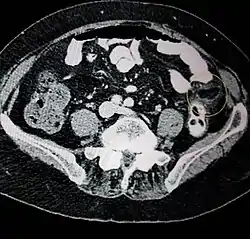

Ultrasound and CT scans are the normal means of positive diagnosis of epiploic appendagitis. Ultrasound scans show "an oval, non-compressible hyperechoic mass with a subtle hypoechoic rim directly under the site of maximum tenderness".[5] Normally, epiploic appendages cannot be seen on CT scan.[5] After cross-sectional imaging and the increased use of abdominal CT for evaluating lower abdominal pain, EA is increasingly diagnosed. Pathognomonic CT scan data represent EA as 2–4 cm, oval shaped, fat density lesions, surrounded by inflammation. Contrasting with diverticulitis findings, the colonic wall is mostly unchanged.

Abdominal CT scan, epiploic appendagitis (circle)